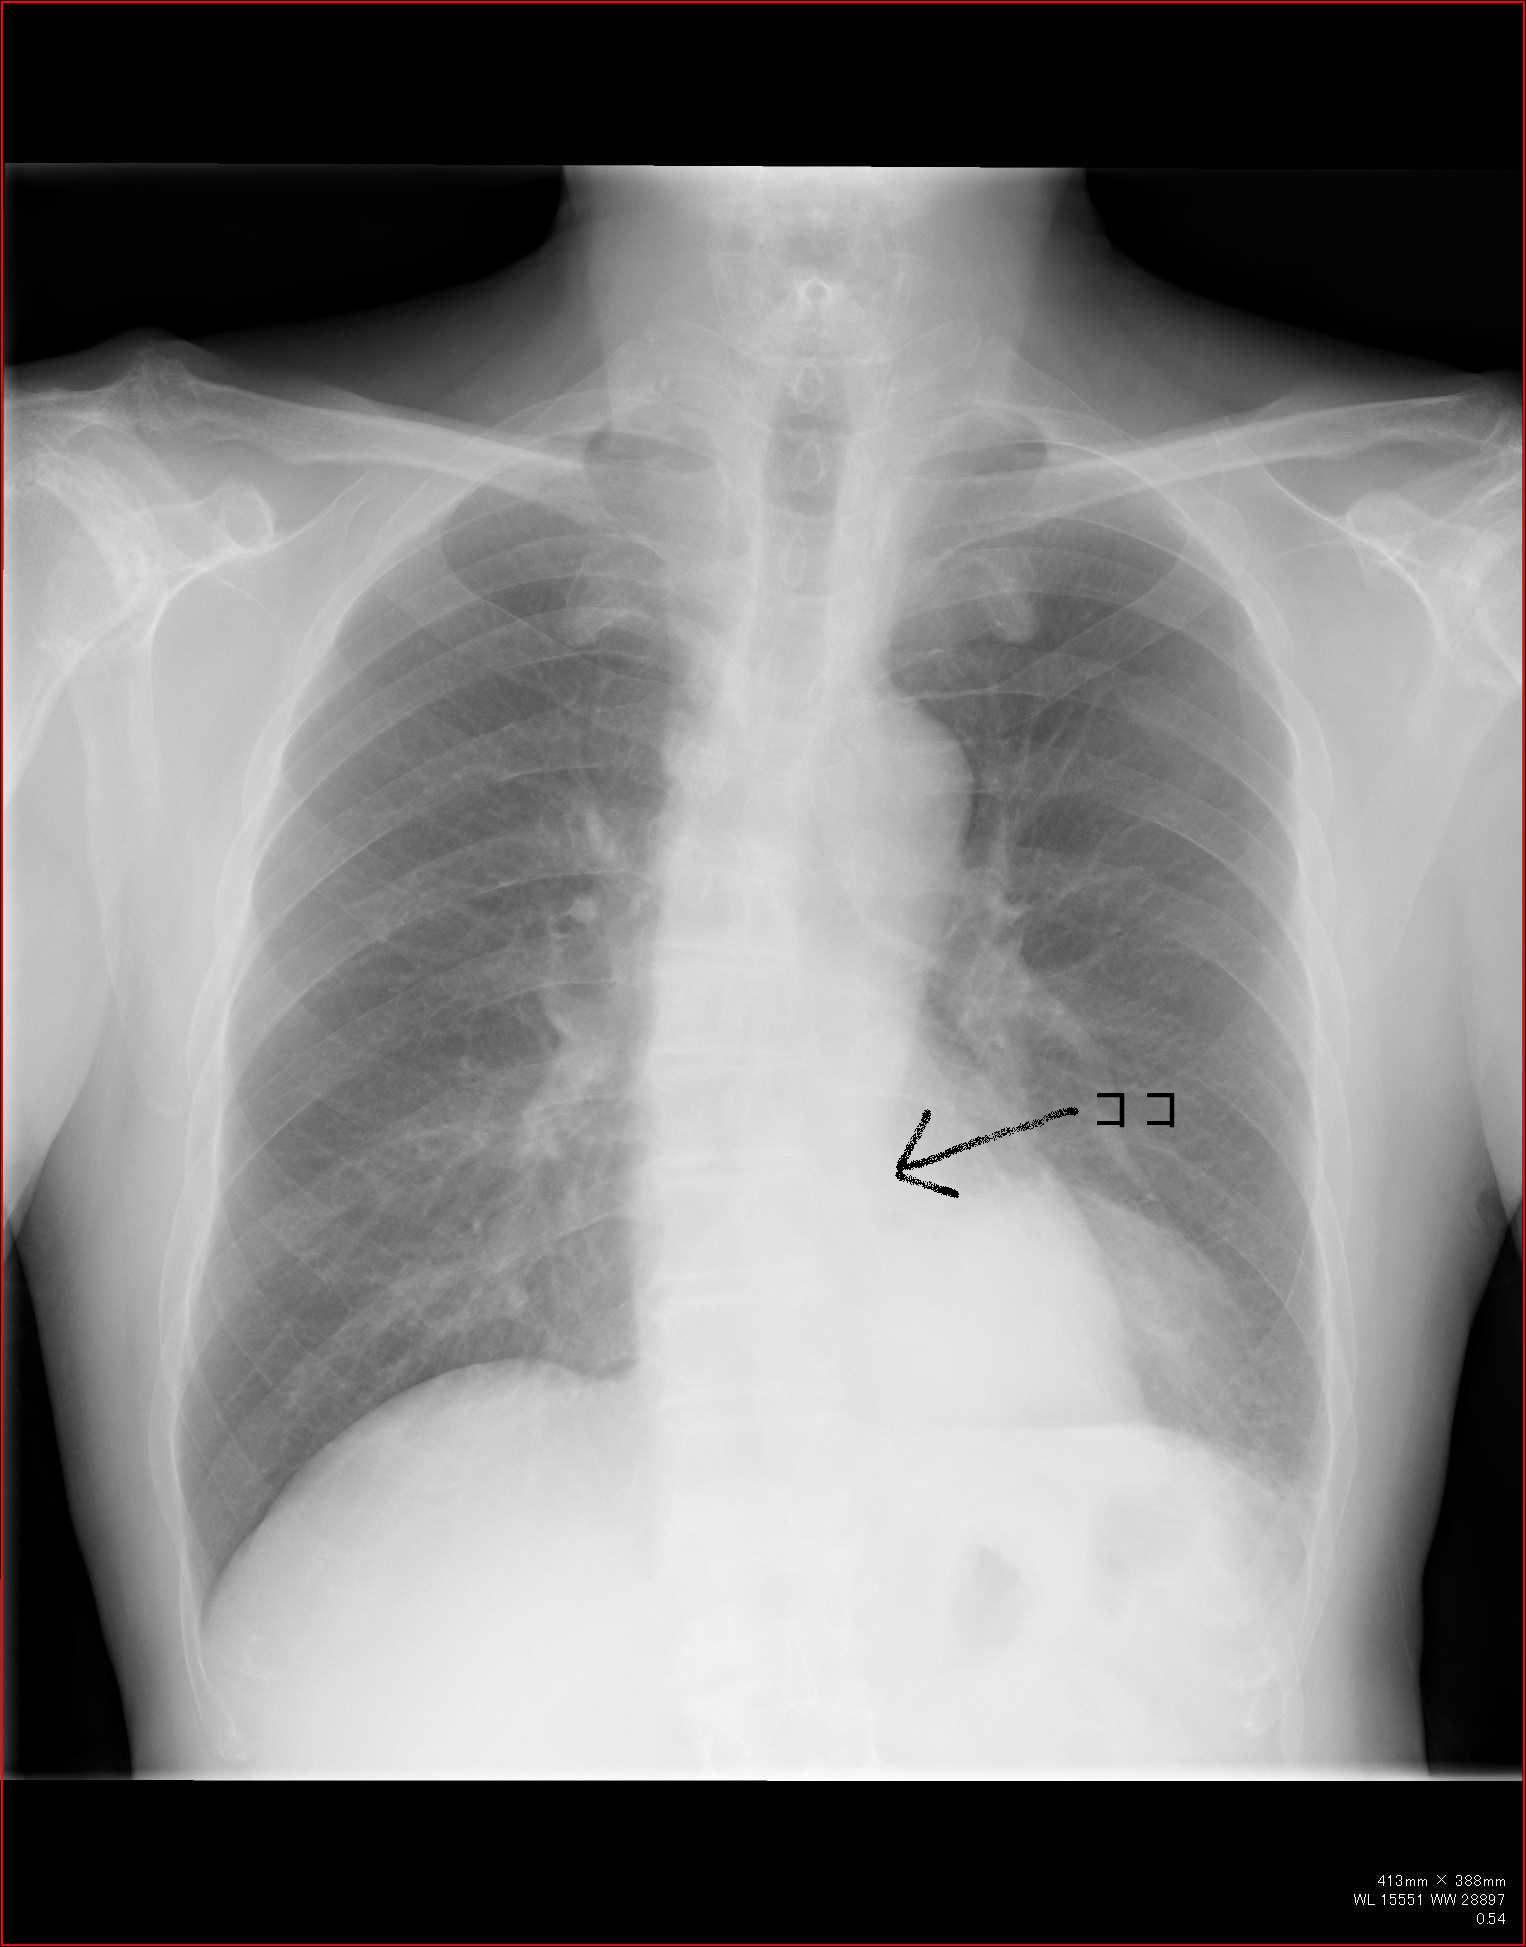

こちらを見て下さい。

わかりにくいかもしれませんが、このあたり。

気管が追いにくい、無くなっているようにも見えます。

気管狭窄ですね。こういう所見もレントゲンで捉えることができるのです。